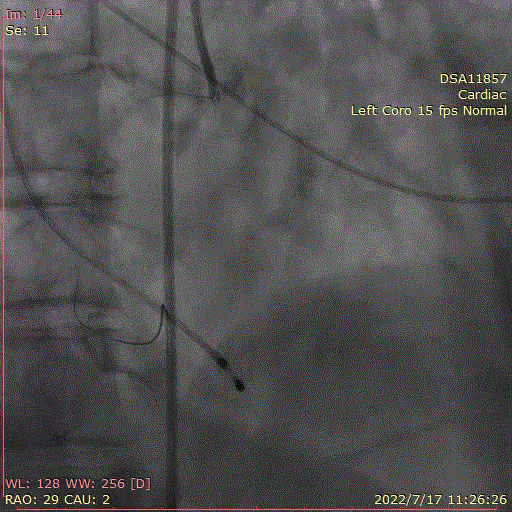

术中首先行冠脉造影术,造影提示右冠近中段严重狭窄,于病变处植入支架一枚。植入后造影显示,无残余狭窄及夹层,前向血流TIMI3级。

冠脉造影,支架植入